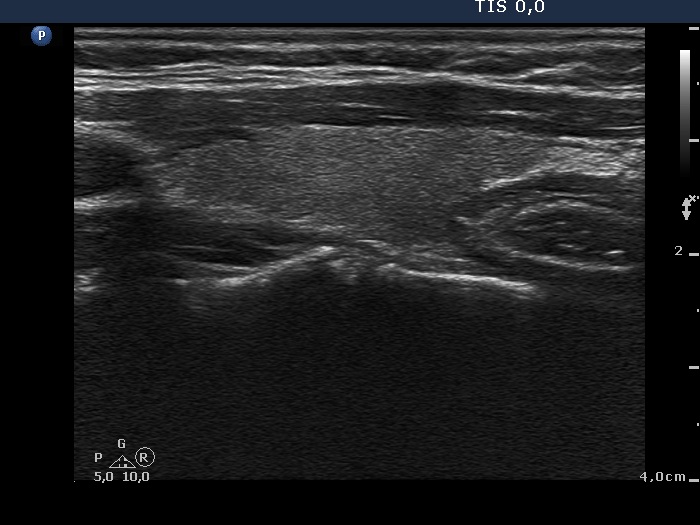

Case 374

6 months after initial investigation (ultrasonographic picture 5)

Left lobe, longitudinal view.